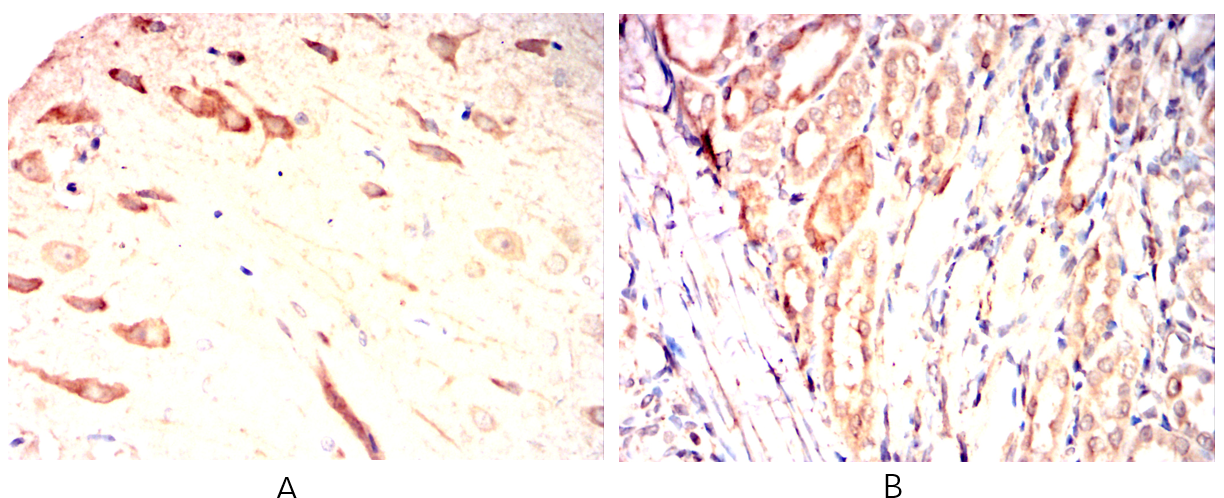

Immunohistochemical analysis of paraffin-embedded Rat brain(A)Rat kidney(B) using SMOC1 mouse mAb with DAB staining